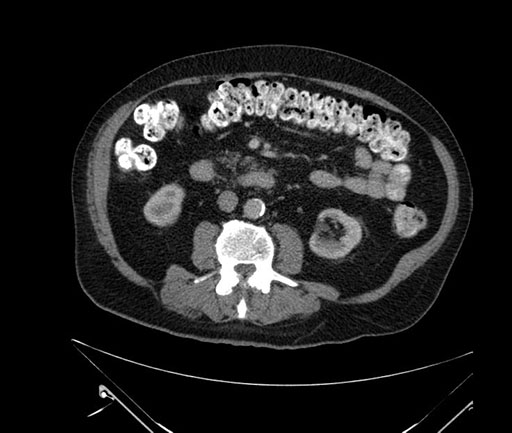

Whipple (pancreaticoduodenectomy) [case 7]

Axial - stented

Coronal - stented

Imaging analysis

Based on your CT findings, which issue(s) would give reason for "planned slowing down moment(s)" in this case?

Considering a standard Whipple procedure, what step(s) of the operation would you do differently in this case?